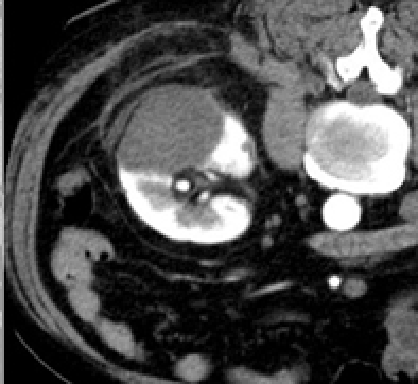

治療前

右腎臓の摘出後の患者さんで、左腎臓にがんができています。治療中では腫瘍が黒い部分で覆われており(赤い印で囲まれた範囲)、氷ができているのがわかります。治療後では腫瘍が壊死しているのがわかります。